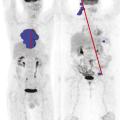

Tomographie par émission de positons : une place centrale dans le bilan et l'évaluation

La tomographie par émission de positons (TEP-scan) est une technique d’imagerie nucléaire fonctionnelle non invasive et désormais largement disponible. Elle est fondée sur l’utilisation d’un radiotraceur radio­actif ciblant un processus biologique, injecté au ­patient, dont la distribution peut ainsi ­être analysée à l’imagerie…

La démarche thérapeutique de première ligne a largement évolué ces dernières années, vers une optimisation du rapport bénéfice-risque. Que la présentation du lymphome de Hodgkin (LH) soit localisée ou avancée, le standard de traitement intègre désormais la tomographie par émission de positons (TEP) pour guider la stratégie, en…